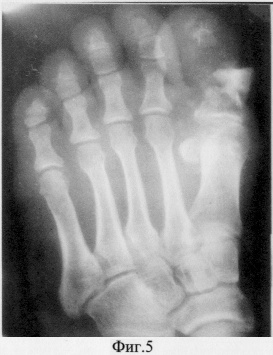

Больная Ю. поступила в клиники ТВМИ (Томск) с диагнозом: Посттравматический остеомиелит основной фаланги 1 пальца правой стопы с обширным некрозом мягких тканей на тыльной ее поверхности (фиг.4, 5).

Длительность заболевания 2 месяца. Остеомиелитический процесс развился после падения на стопу трубы с размозжением мягких тканей и основной фаланги 1 пальца. После предоперационной подготовки, включавшей в себя антибиотикотерапию, противовоспалительное, обезболивающее лечение, сосудистую терапию, гипербарическую оксигенацию выполнена операция, согласно предлагаемому способу.